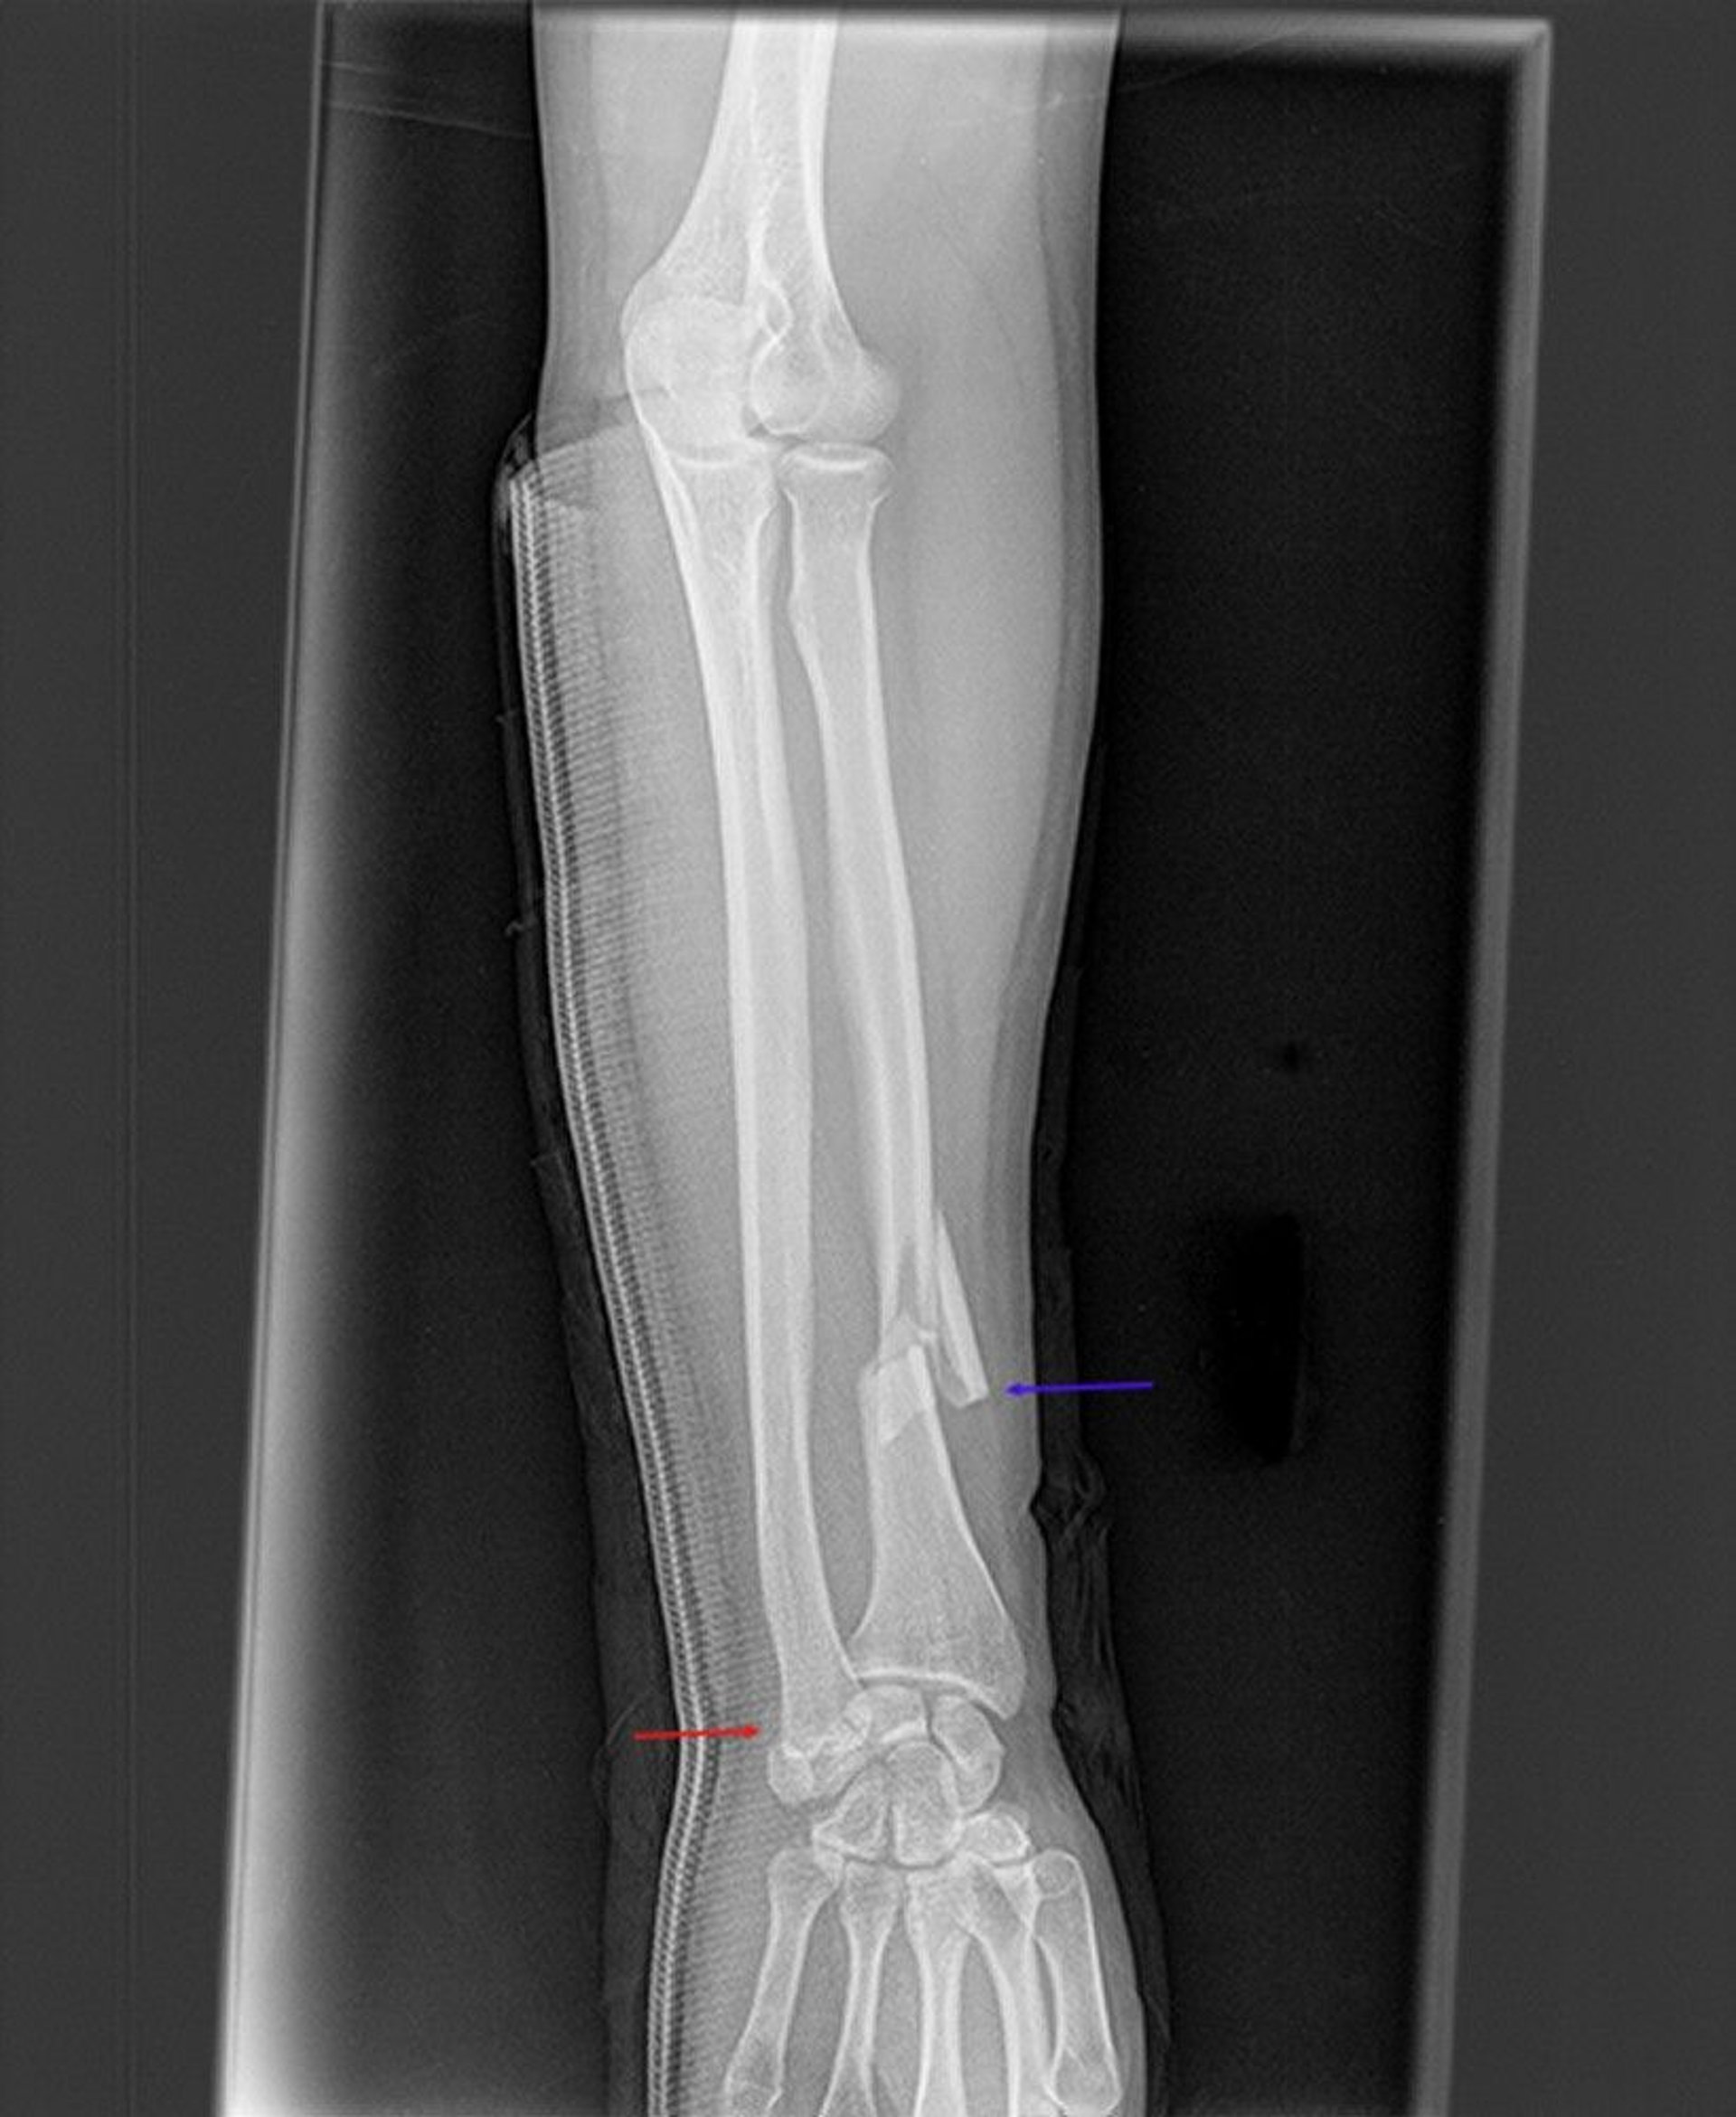

Galeazzi Fracture

This radiograph shows a fracture of the distal radius (blue arrow) and disruption of the distal radioulnar joint (red arrow). The articular surfaces of the distal ulna and distal radius are not aligned with each other.

Image courtesy of Danielle Campagne, MD.